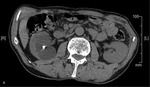

W związku z podejrzeniem występowania rozrostu w obrębie torbieli nerki u chorego w trybie ambulatoryjnym wykonano wielofazowe badanie metodą tomografii komputerowej (TK) jamy brzusznej (faza przeglądowa, faza tętnicza, korowo-rdzeniowa 30-50 s po dożylnym podaniu środka cieniującego i późna faza pokontrastowa, faza wydzielnicza, ok. 3-5 min po podaniu środka cieniującego).1 W badaniu potwierdzono występowanie w obu nerkach kilku zmian o cechach torbieli, zaś w obrębie nerki lewej torbieli z położonym obwodowo obszarem wzmocnienia pokontrastowego (ryc. 2A-D).

Dodatkowo nie stwierdzono cech adenopatii i zmian ogniskowych w wątrobie.